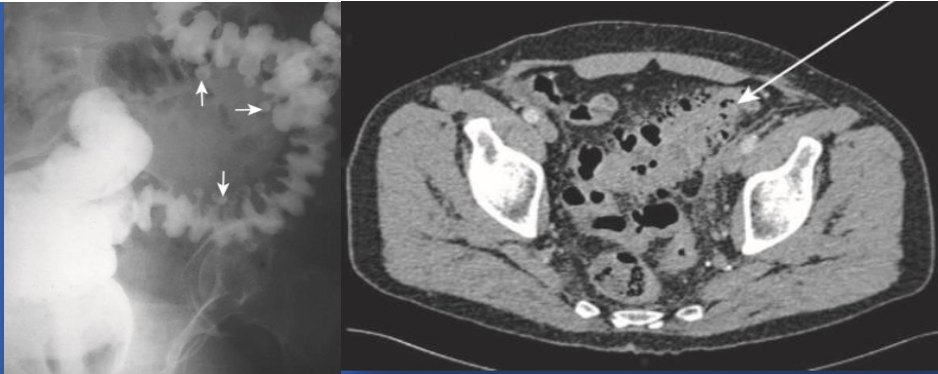

Radiology images:

Contrast enema, * Water-soluble medium, * Mild-to-moderate uncomplicated cases

CT abdomen with contrast * Best imaging method to confirm the diagnosis. * Sensitivity and specificity 97% * Bowel wall thickening * Soft-tissue inflammatory masses * Complications, exclude other pathology